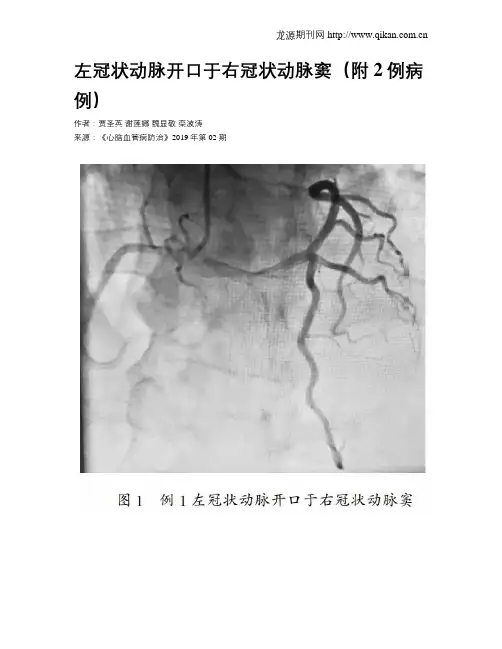

进一步行冠状动脉造影检查提示左主干开口于右冠状动脉窦,冠状动脉无狭窄及阻塞性病变,证实为冠状动脉起源异常(左右冠状动脉共开口),附图1。

本文就冠状动脉造影检查发现的2例左冠状动脉起源于右冠状动脉窦(即左右冠状动脉共开口)病例报道如下:1;病例介绍例1:患者男,79岁,胸部不适1周为主要表现,非典型缺血性胸痛表现。